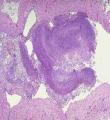

肺麴黴病,多發生於家禽飼養員和有關人員。麴黴侵入肺組織而發生壞死性支氣管肺炎,侵入肺空洞或擴張的支氣管形成麴黴球。本病確診需依靠病原學檢查。變態反應性肺麴黴病經脫離與麴黴接觸,避免吸入麴黴孢子後,病情可自行緩解。肺麴黴球一般用手術治療。支氣管-肺炎型和繼發性肺麴黴病為難治的麴黴病之一,用抗真菌藥及支持對症療法有一定效果。